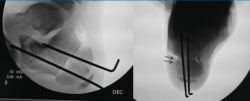

El calcáneo stop es un procedimiento mínimamente invasivo que consiste en limitar la RE-valgo del BCP y, por tanto, la subluxación del astrágalo en medial(12). Se hace mediante reducción en varo y colocación de un tornillo en el surco del calcáneo (fondo del ángulo de Gissane), cuya cabeza crea impingement con el proceso lateral del astrágalo en valgo (Figura 11).

Figura 11. Técnica de calcáneo stop. A: mínima incisión (1,5 cm), liberación del seno del tarso; B y C: colocación de aguja de Kirschner en el surco del calcáneo delante de la parte anterior del proceso lateral del astrágalo, con el pie en varo; D: posición de la cabeza del tornillo que hace impingement con el proceso lateral del astrágalo en valgo; E y F: imágenes radiológicas intraoperatorias, visualizando la orientación del tornillo de 30° en el plano sagital y 10° en el plano coronal.